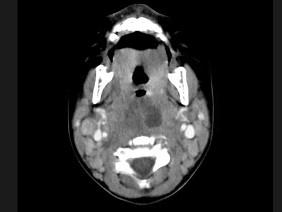

问题 10个月大的婴儿,发热,曾患中耳炎,CT扫描如图所示,请选择正确的描述或诊断 ( )

选项 A、考虑为咽后壁脓肿 B、考虑为咽后壁寒性脓肿 C、其内密度不均 D、颈椎骨质未见明显异常 E、咽后壁软组织肿胀

答案 ACDE